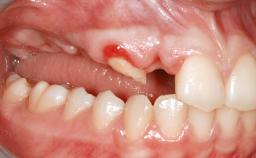

Shell Technique for Horizontal and Vertical Maxillary Bone Augmentation in a Partially Edentulous Patient with Aggressive Periodontal Disease

A 46-year-old woman was referred for treatment whose main complaints were mobility of her fixed partial dentures (right maxilla and left mandible) and periodontal bleeding during function. She also reported having taken systemic antibiotics to treat recurrent swelling in the area of the upper left molars. The patient had not seen a dentist for at least 2 years. She did not smoke and had no history of major systemic disease other than two minor orthopedic procedures some years back. The first-visit examination revealed poor plaque control, tooth mobility, periodontal disease, and a residual dentition widely associated with deep periodontal pockets.

Infection at Implant Site None Chronic Acute

Bone Volume Horizontally and vertically sufficient Horizontally deficient Deficient vertically or deficient vertically AND horizontally